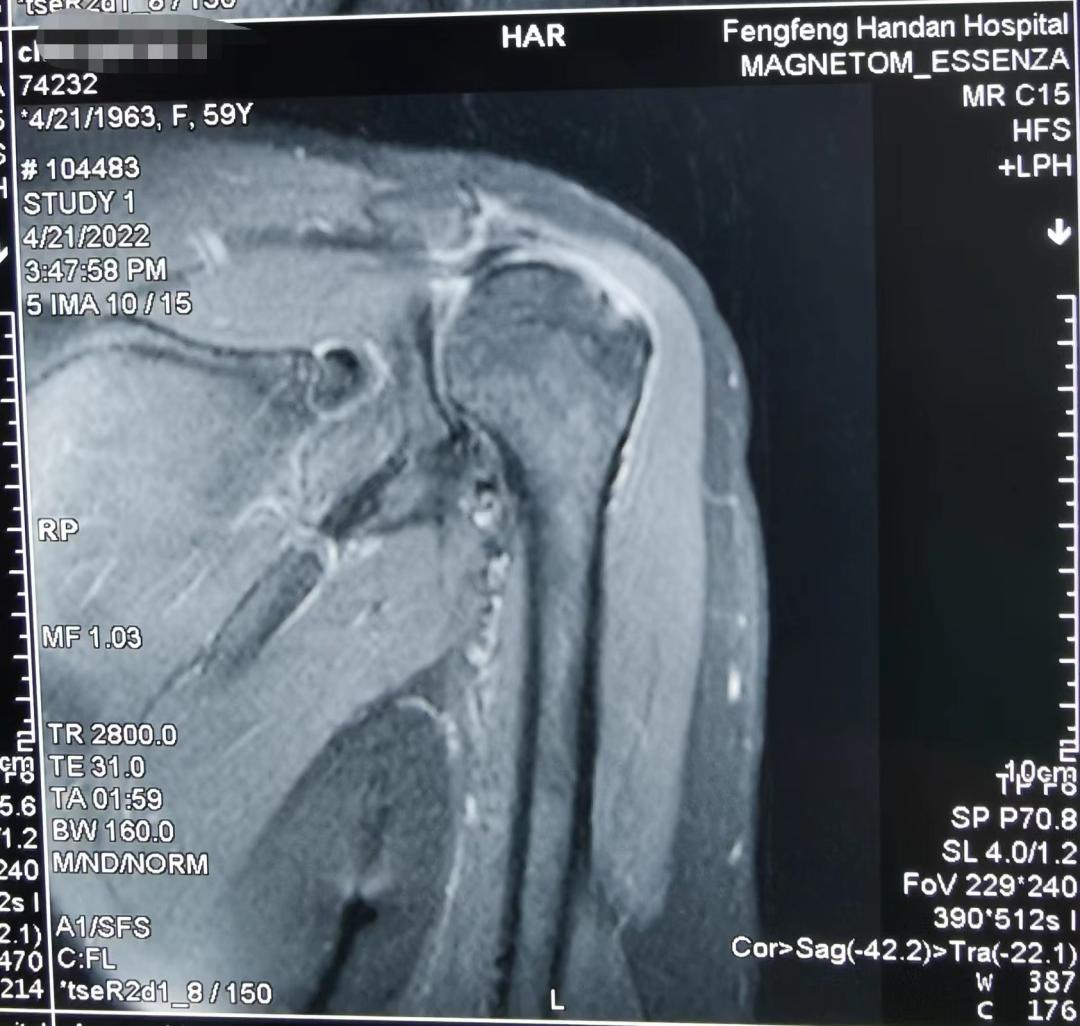

MRI 结果显示:左侧巨大肩袖损伤(冈上肌和冈下肌腱),肩峰撞击,关节粘连。保守治疗并不能缓解患者左肩疼痛症状,王主任以及主管大夫高小康决定全麻下行 肩关节镜下肩袖缝合,肩峰成型,粘连松解术 。

图一